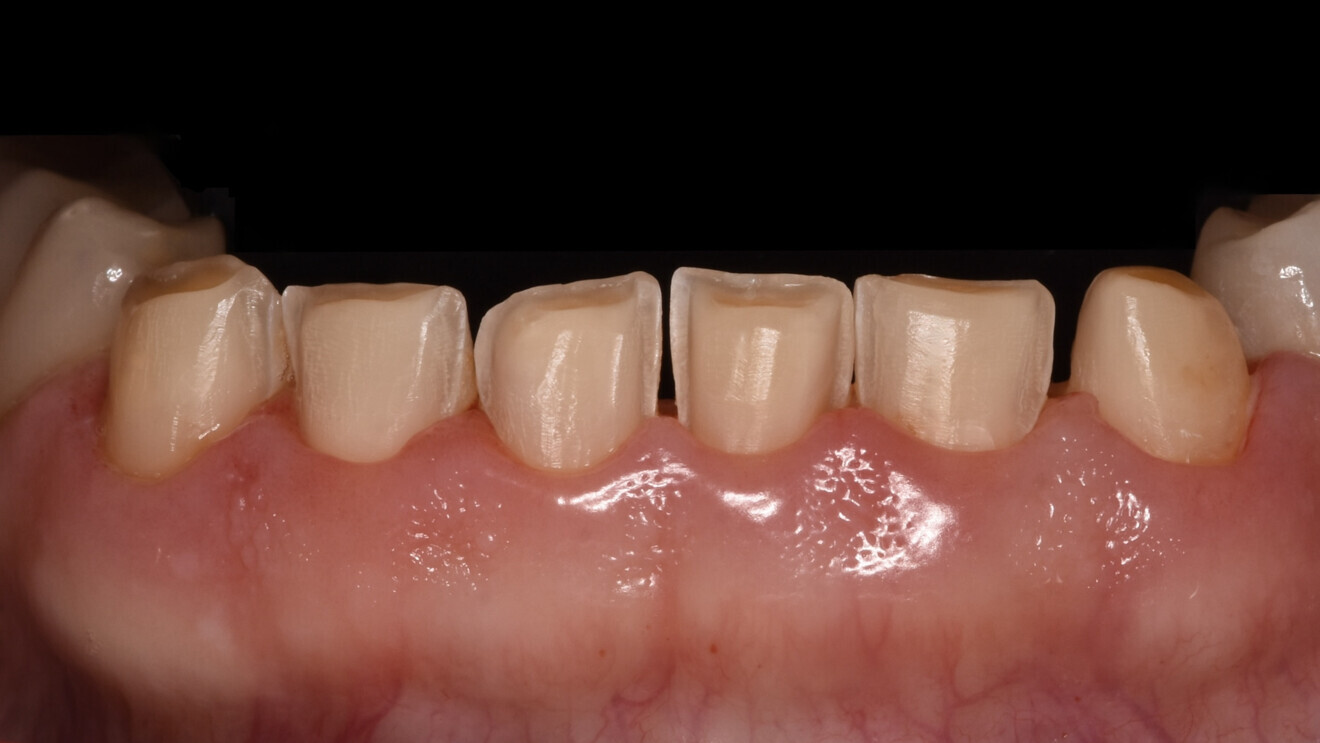

Fig. 1e: Almost complete loss of the occlusal relief in the lower jaw.